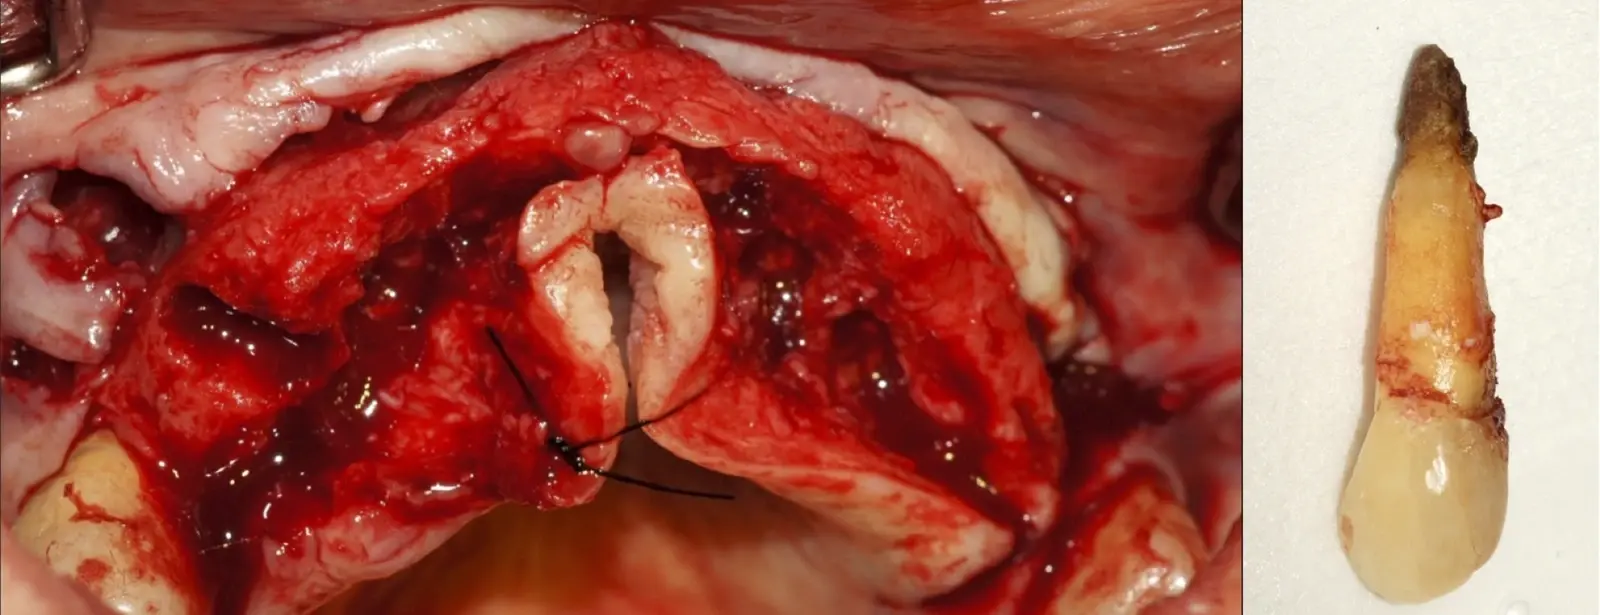

El procedimiento se inicia colocando anestesia y elevando un colgajo mucoperióstico a espesor completo3 (incisión semilunar o intrasurcular con/sin protección papilar) y exponiendo la zona. En seguida se realiza la enucleación de la lesión, eliminando16 o creando una ventana17 en la lámina cortical que contiene el área del ápice; este retiro óseo se realiza con los insertos de forma aplanada dentada o inserto con cobertura diamantada plano o redondo, recordando ser lo más conservador posible (Figura 5).

Después de realizado el acceso e identificado el ápice, se procede a la limpieza de la zona con instrumentos manuales y/o con insertos diamantados de parte activa angulada para poder eliminar todo el tejido patológico del perímetro radicular apical y del tejido óseo circundante (Figura 6).

Una vez limpia la zona apical, se corrobora la integridad de la raíz y se evalúa el grado de extensión de la lesión. Si el defecto óseo es pequeño, se procede a realizar la preparación del conducto y obturación retrógrada de ser el caso. Si el defecto óseo es de gran tamaño e inaccesible a los insertos, se procede a realizar un corte de por lo menos 3 mm de ápice radicular conteniendo los posibles conductos aún infectados11 empleando habitualmente insertos de borde aserrado con/sin marcas de medición para un trabajo seguro7 (Figura 7).